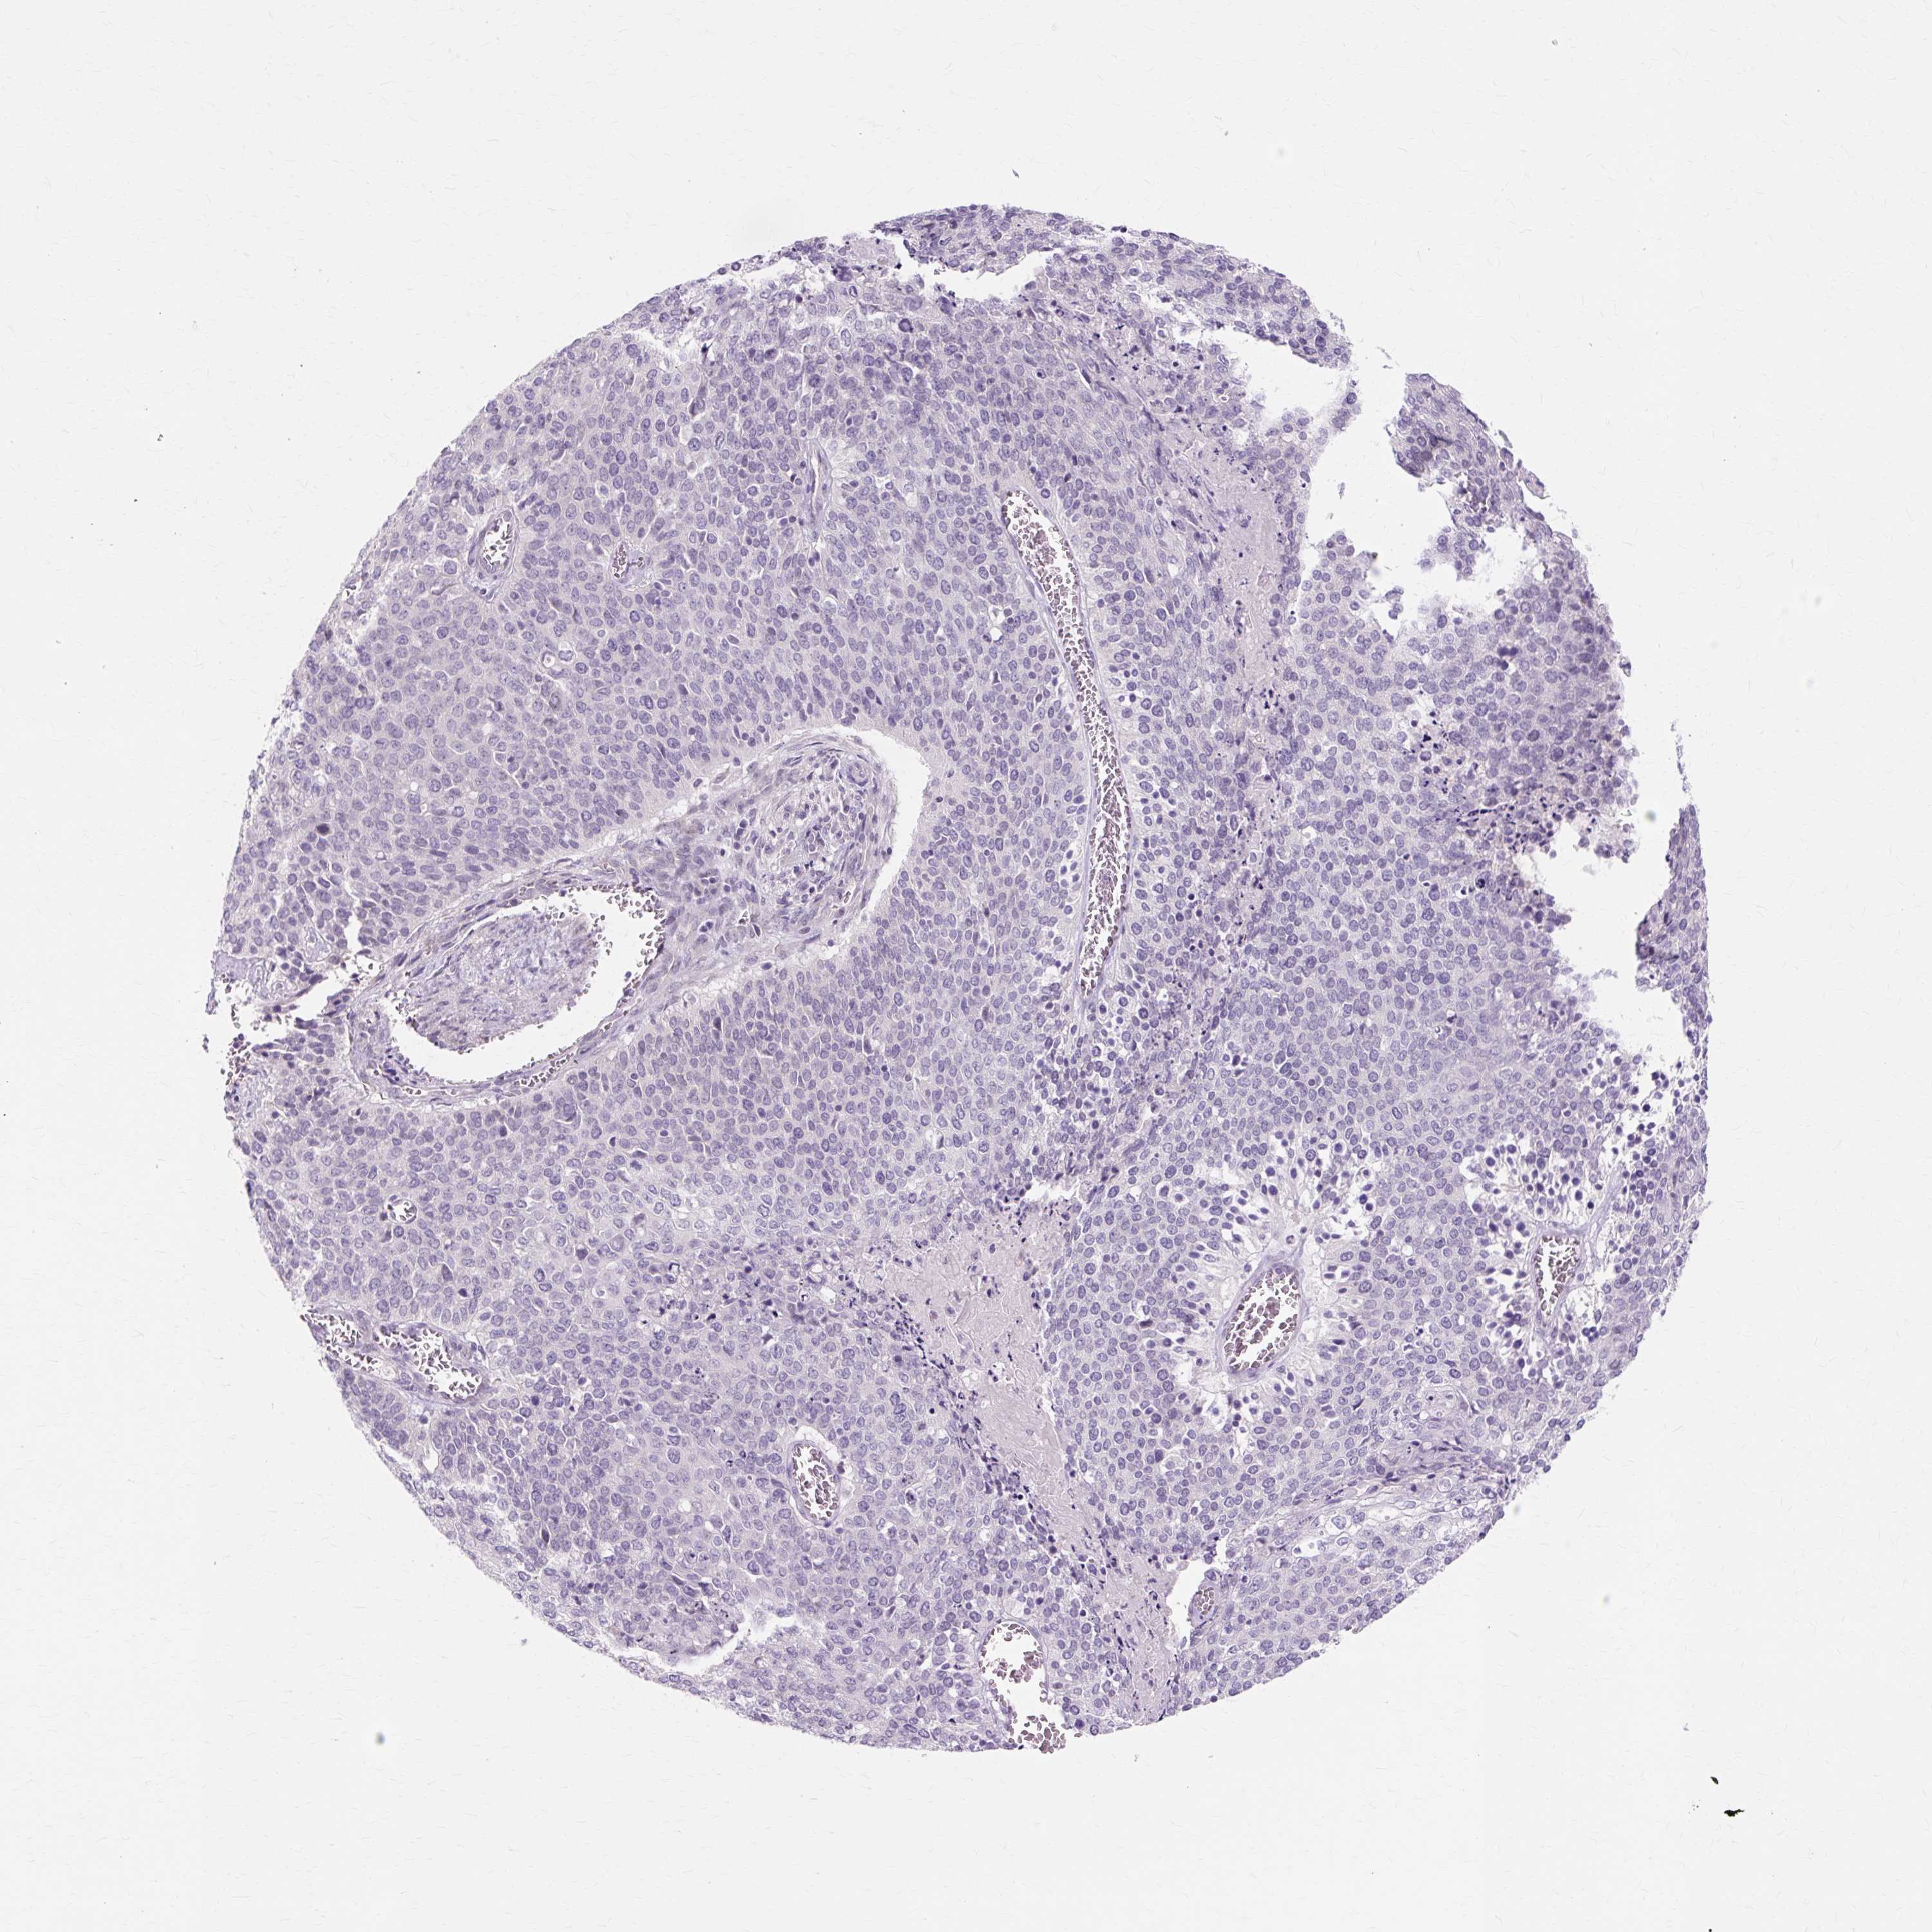

CERVICAL CANCER - Protein expressioni

A mouse-over function shows sample information and annotation data. Click on an image to view it in a full screen mode. Samples can be filtered based on level of antibody staining by selecting one or several of the following categories: high, medium, low and not detected. The assay and annotation is described here.

Note that samples used for immunohistochemistry by the Human Protein Atlas do not correspond to samples in the TCGA dataset.

Antibody stainingi

Antibody staining in the annotated cell types in the current human tissue is reported as not detected, low, medium, or high, based on conventional immunohistochemistry profiling in selected tissues. This score is based on the combination of the staining intensity and fraction of stained cells.

Each image is clickable and will lead to virtual microscopy that enables deeper exploration of all samples and also displays staining intensity scores, fraction scores and subcellular localization as well as patient and tissue information for each sample.

Antibody HPA051859

Antibody HPA054738

Staining

High

Medium

Low

Not detected

Intensity

Strong

Moderate

Weak

Negative

Quantity

>75%

75%-25%

<25%

None

Location

Nuclear

Cytoplasmic/membranous

Cytoplasmic/membranous,nuclear

Squamous cell carcinoma, NOS

Adenocarcinoma, NOS